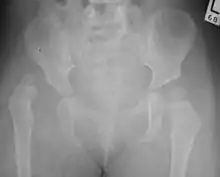

| Congenital dislocation of the left hip in an elderly person. Closed arrow marks the acetabulum, open arrow the femoral head. | |